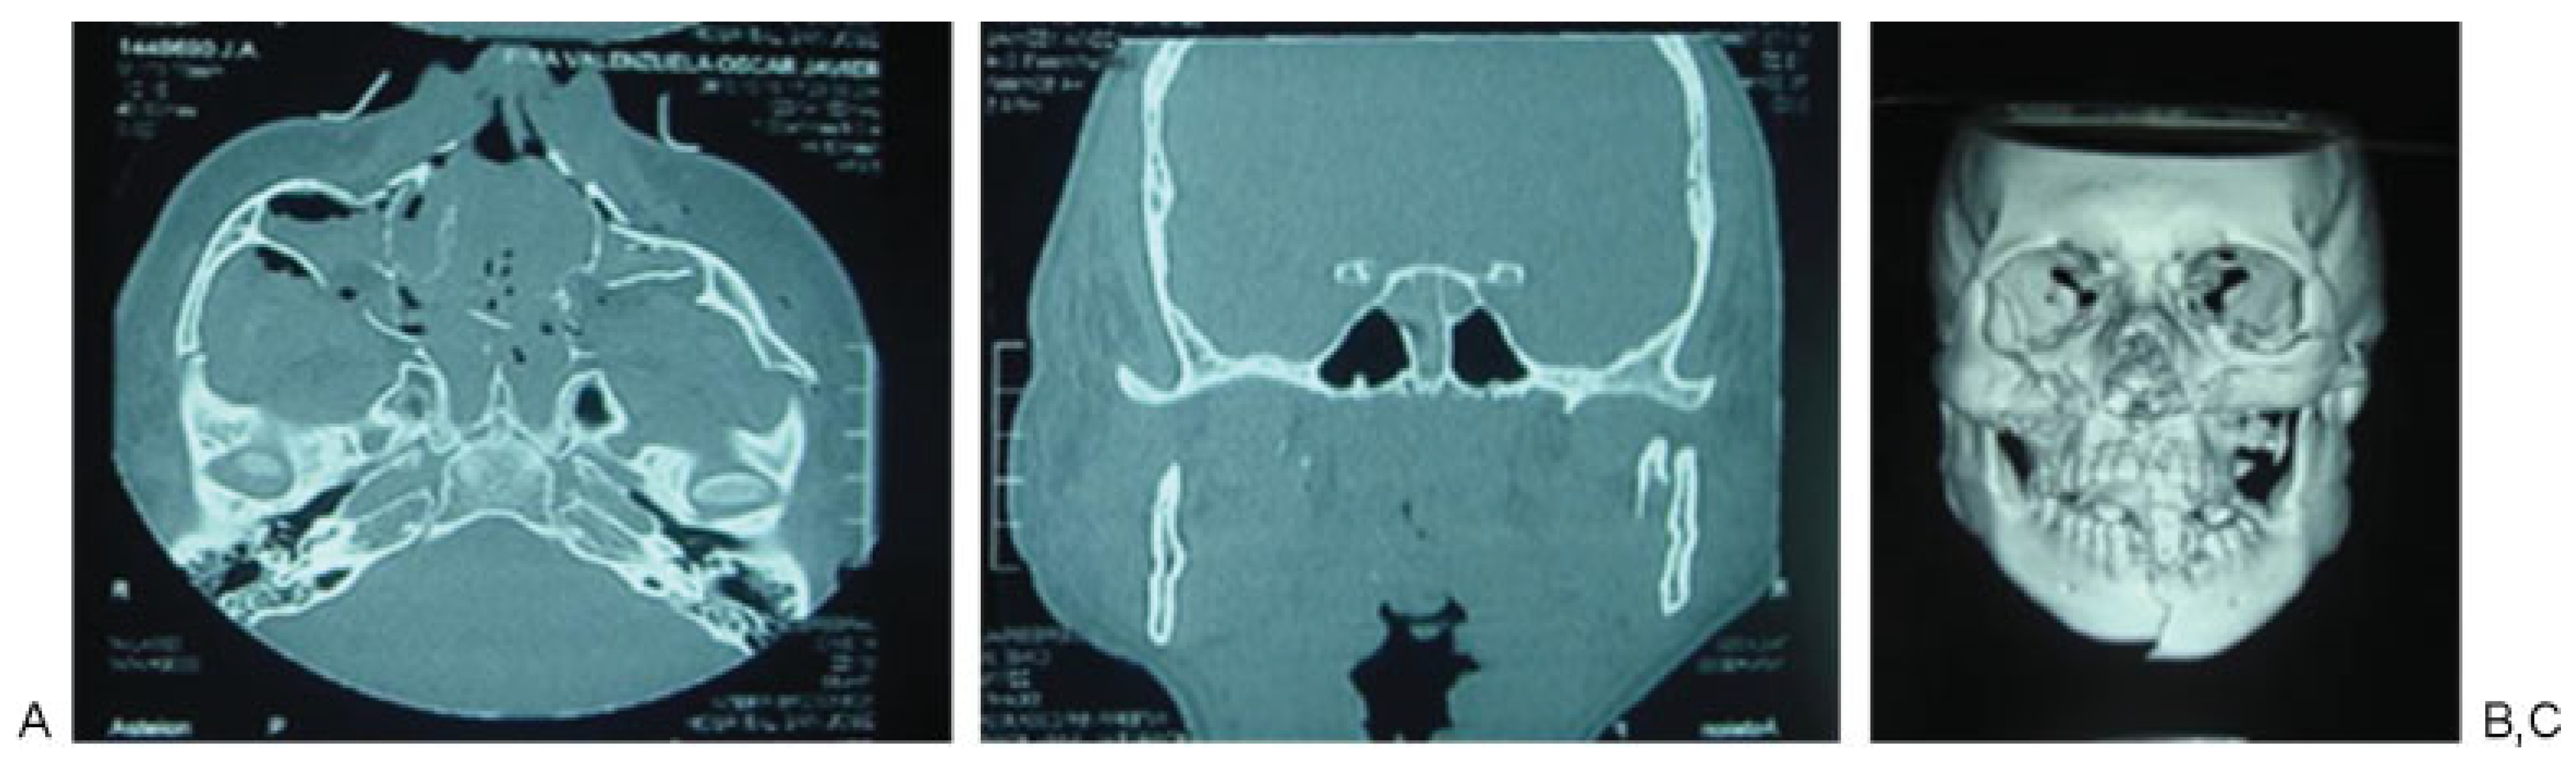

According to Manson’s classification, 17.9% (n ¼ 38) of the trauma in the group corresponded to high-energy trauma, followed by medium-energy trauma at 33.5% (n ¼ 71) and low-energy trauma at 48.6% (n ¼ 103). Among the patients with high-energy trauma, 31.5% (n ¼ 12) had combined fractures of the sphenoid bone and sphenoid sinus and 31.5% (n ¼ 12) had sphenoid sinus fractures only. In contrast, 1.4% (n ¼ 3) of patients with middle-energy trauma had sphenoid bone fractures, 5.6% (n ¼ 4) of the patients had sphenoid sinus fractures, and 4.2% (n ¼ 3) of the patients had sphenoid bone and sphenoid sinus fractures. In the low-energy trauma group, only 1 patient presented sphenoid sinus fracture (0.97%; Table 3; Figure 2, Figure 3 and Figure 4).

Figure 2. Patient 1: high-energy trauma and panfacial fractures. (A) Zygomatic arch, malar, and upper jaw fractures. (B) Sphenoid sinus fracture. (C) Computed tomography three-dimensional reconstruction showing the fractures at the middle third and jaw.